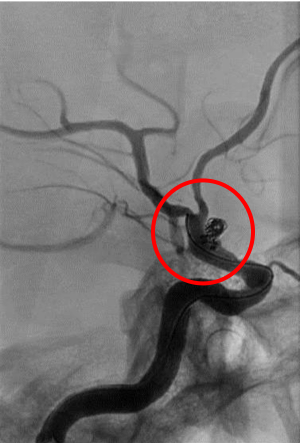

脳動静脈奇形(AVM)

脳の動脈が毛細血管を介さずに「ナイダス」と呼ばれる血管のかたまりで直接静脈につながっており、動脈血が直接静脈に流入している病気です。脳出血、くも膜下出血、けいれん発作の原因となることがあります。治療には開頭摘出術、脳血管内手術(塞栓術)、放射線治療があり、これらを組み合わせた集学的治療が必要な場合も多くあります。

術前の造影写真です。〇内に脳動静脈奇形が描出されています。

塞栓術および摘出術後の造影写真です。脳動静脈奇形は消失しております。